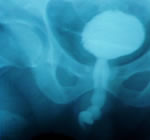

- Цистография - контраст заполняет

простатическую, перепончатую часть и проксимальный

отдел бульбозной уретры, предполагаемый дефицит

уретры 1-1,5 см.